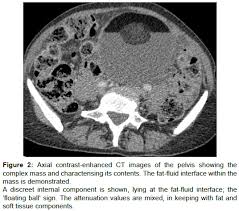

Sonographic Assessment Of Ovarian Cysts And Masses Chapter 8 Gynaecological Ultrasound Scanning from static.cambridge.org I was also diagnosed with diverticulosis following a ct a year before final diagnosis of stage 3 ovarian cancer. Can 19mm ovarian dermoid cyst be mistaken (misdiagnosed) with any another cysts? However, as women, this is something we need to be talking about. Malignant ovarian cysts are only seen in rare cases, with the benign being the most common of them all. A healthy ovary and one from a woman with pcos. Hi, my gyno told me that i had a dermoid cyst, even after my ca 125 test results were 2274. If you have a history of breast or ovarian cancer in your family, tell your ob/gyn so they can check for symptoms early on. They are often harmless and require no treatment.

Ovarian Cancer And Cysts What Is The Link from post.medicalnewstoday.com If there are clues that this mass could be cancer, you will be referred to a cancer surgeon (a gynecologic oncologist) for further examination and consultation. The ratio of cancers caused by dermoid cyst among malignant germ cell ovarian tumors is 2.9% (1, 2). It is a benign tumor that usually affects women of reproductive age (teens through forties). The dermoid ovarian cyst is sometimes called an ovarian neoplasm or dermoid cyst on the ovary. He doesn't think my reflux problem is related to my pelvic pain. Dermoid cysts are also known as mature teratomas. The cyst can also lead to a twisting of the ovary ( torsion ). The cancer surgeon can remove the mass, and if it is determined to be cancer, can also remove lymph nodes to see if the cancer has spread.